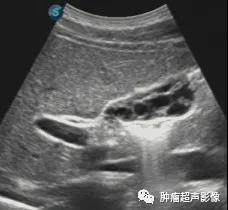

蜂巢样胆囊:胆囊内见多处的细薄分隔,将胆囊全部或局部分隔为大小不等的囊腔结构,断面上类似于蜂巢,故得名。 蜂巢样胆囊的发病原因尚不清楚,一般考虑为先天发育异常,部...